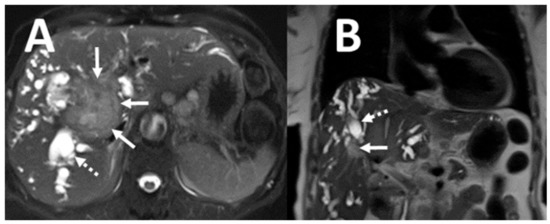

| Cholangiocarcinoma | 7 (28) |

| Hepatocellular carcinoma | 3 (12) |